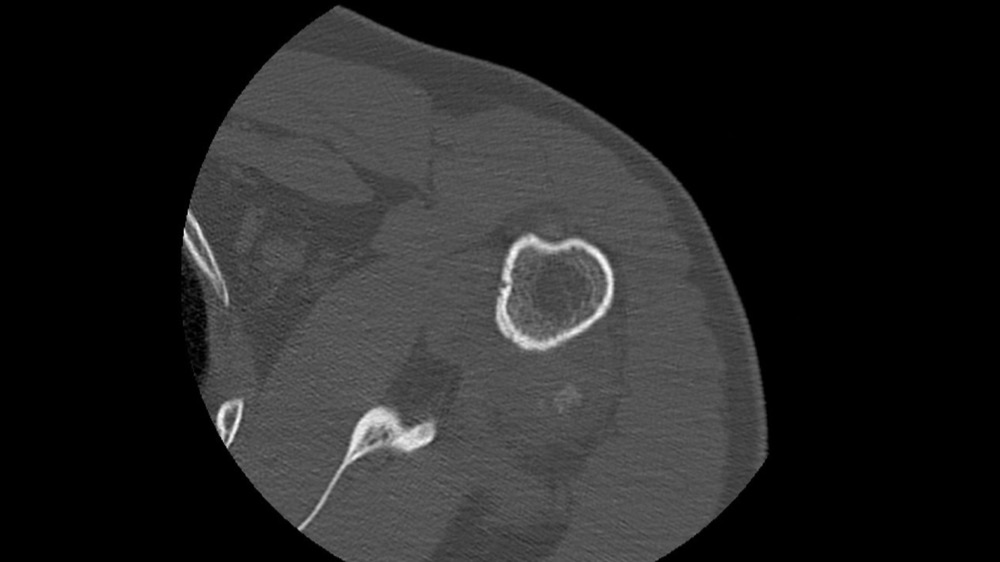

Gortais / Biyoukar / Miquel / Parlier-Cau 19/01/2022